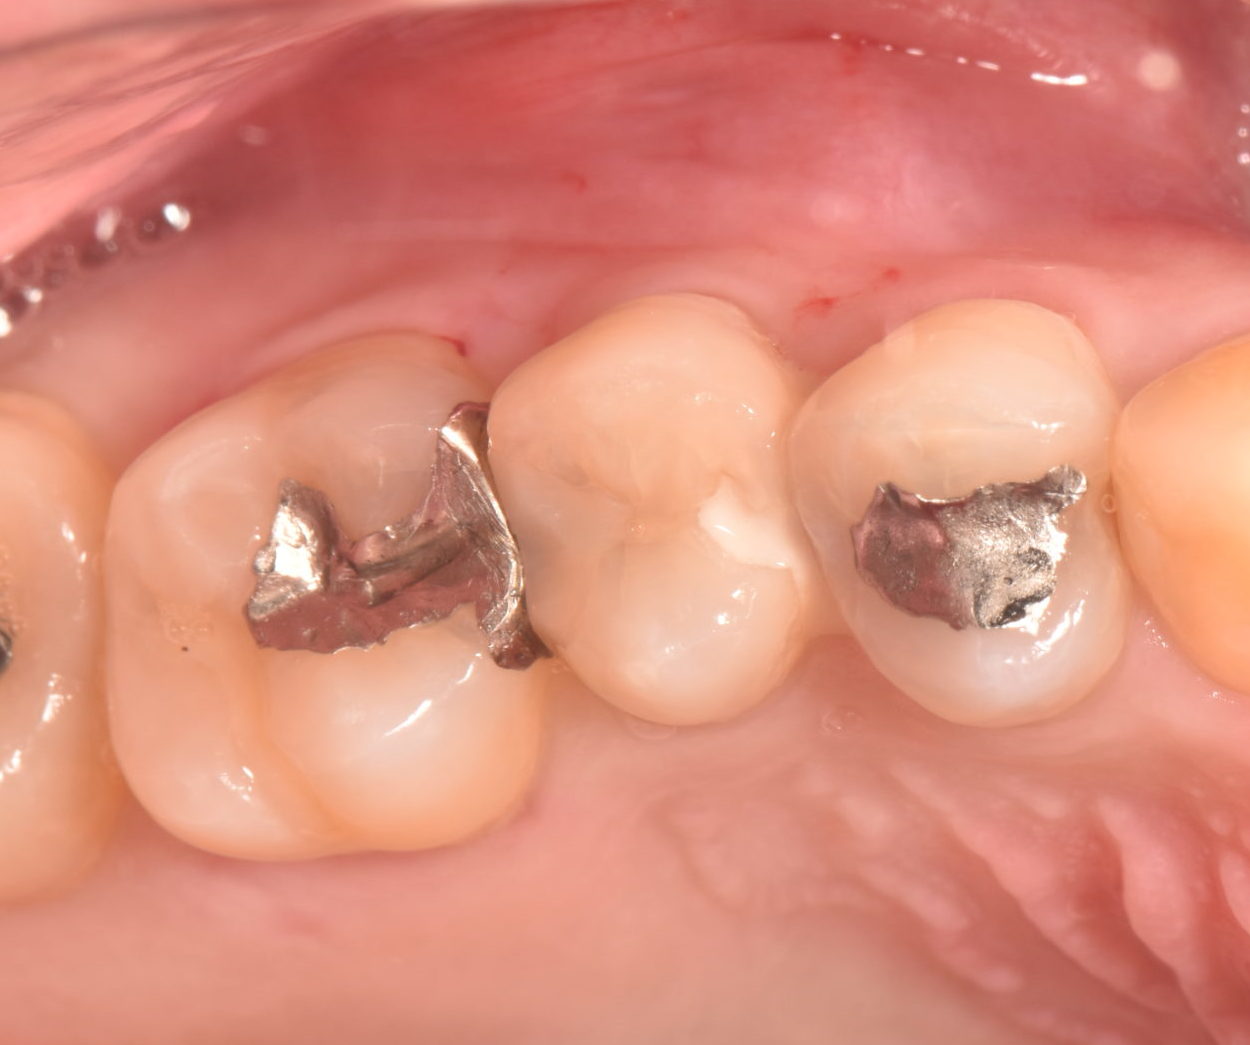

仮封の状態で数日間経過観察を行い、異常はみられなかったためダイレクトボンディングにて歯冠修復を行った。

歯髄の保護を行った後は経過観察を行い、臨床症状がないことを確認し詰め物や被せ物にて修復治療を行います。

今回の症例では歯質も十分に残っていたり、咬合も強くは当たらなかったことからダイレクトボンディングという詰め物を行っています。http://www.kawano-dental-clinic.jp/column/21/